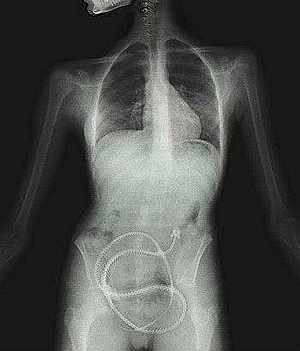

Una mujer de Iowa, Estados Unidos, compró una lombriz solitaria por internet y se la tragó con el único propósito de perder peso.

La mujer, a los pocos días de introducir el parásito en su estómago comenzó a sentir dolores, razón por la que consultó al médico. La sorpresa fue mayúscula tras la confesión y el doctor que la atendió quedó tan impactado que llamó al departamento de Salud Pública para que lo guiaran.

«Ingerir lombrices solitarias es extremadamente peligroso y podría causar una gran cantidad de efectos secundarios indeseables, incluyendo la muerte», escribió Quinlisk.

Si bien las lombrices solitarias pueden aparecer en el cuerpo humano al consumir carne cruda, no es conveniente introducirlos de forma voluntaria al estómago porque puede absorber suficiente comida como para provocar desnutrición.